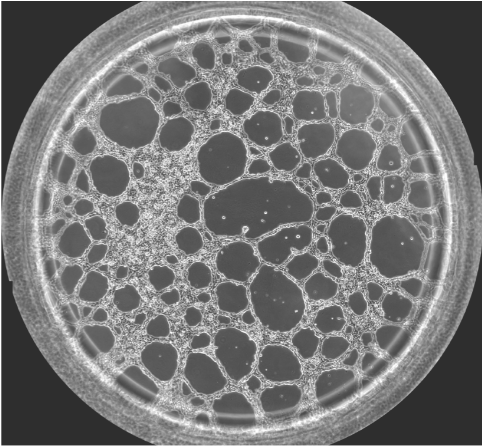

圖一 血管生成鏡檢圖

無論原發(fā)性腫瘤還是繼發(fā)性腫瘤,一旦生長直徑超過1~2 mm,都會有血管生成。這是由于腫瘤細胞自身可分泌多種生長因子,誘導血管生成。多數(shù)惡性腫瘤的血管生成密集且生長迅速。因此,血管生成在腫瘤的發(fā)展轉(zhuǎn)移過程中起到重要作用,抑制這一過程將能明顯阻止腫瘤組織的發(fā)展和擴散轉(zhuǎn)移。于是體外的血管生成實驗就能很好的模擬腫瘤的血管發(fā)生過程,并且適合研究藥物對這一過程的影響實驗。本實驗以HUVEC細胞為例,介紹這一實驗的詳細過程。

可以按照細胞的生長速度定時采集圖像,并且對其成管長度,覆蓋面積,成環(huán)數(shù),結(jié)點數(shù)進行測量和記錄,并且對其進行統(tǒng)計分析。